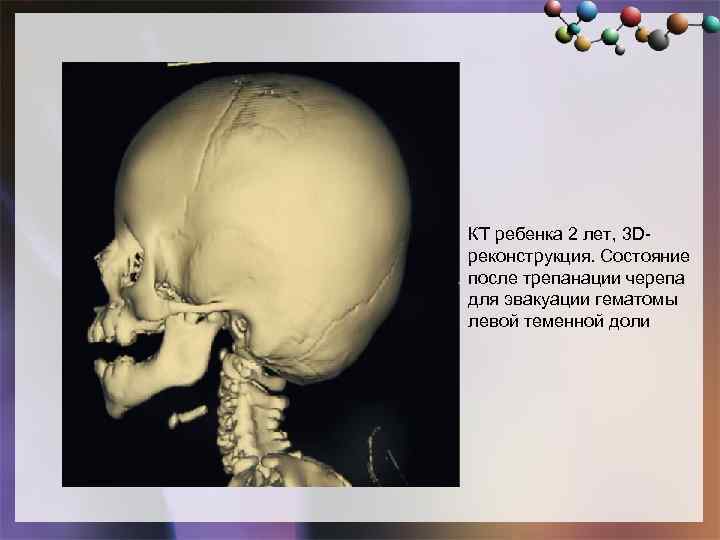

КТ ребенка 2 лет, 3 Dреконструкция. Состояние после трепанации черепа для эвакуации гематомы левой теменной доли

КТ ребенка 2 лет, 3 Dреконструкция. Состояние после трепанации черепа для эвакуации гематомы левой теменной доли